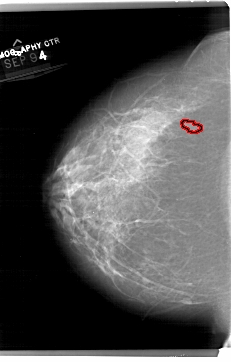

FILE: A_1514_1.LEFT_CC.OVERLAY

TOTAL_ABNORMALITIES 1

ABNORMALITY 1

LESION_TYPE MASS SHAPE IRREGULAR MARGINS ILL_DEFINED

ASSESSMENT 4

SUBTLETY 2

PATHOLOGY BENIGN

TOTAL_OUTLINES 1

BOUNDARY